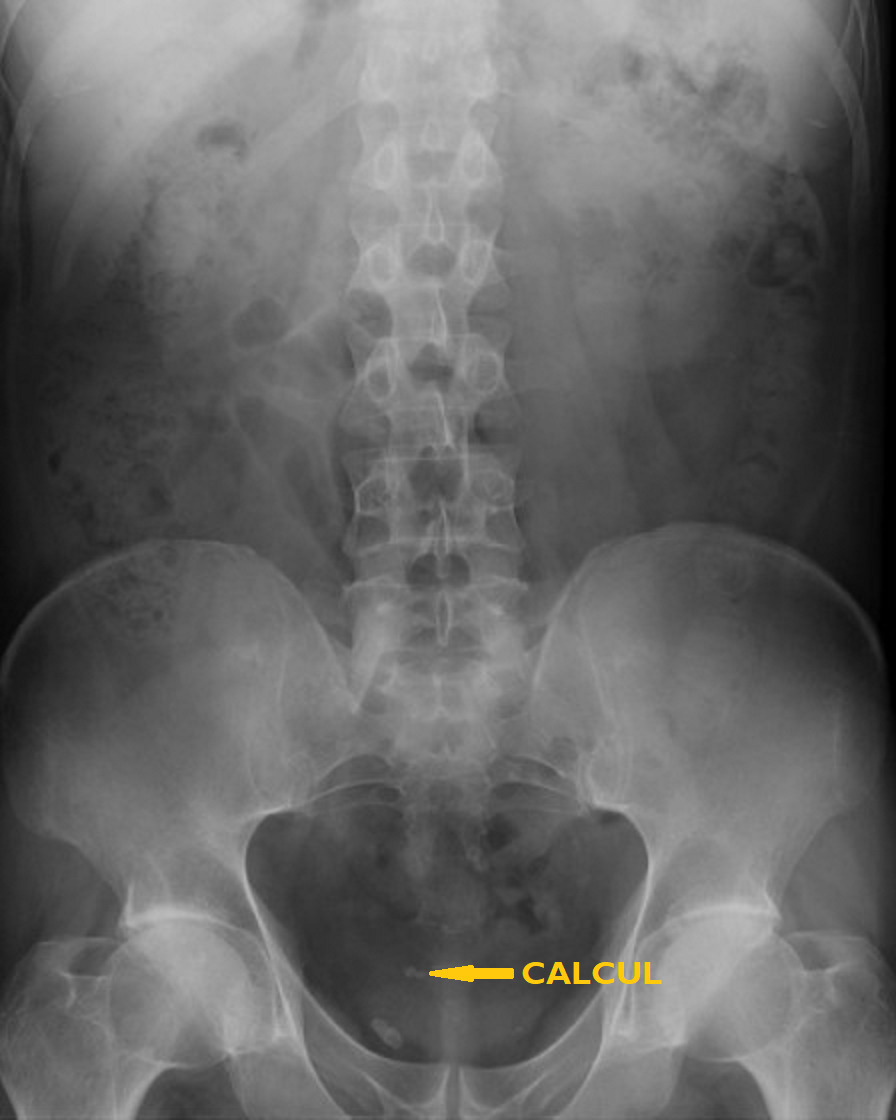

• en cas de calcul, de déterminer sa taille et sa localisation (impact pronostique important pour l’expul­sion spontanée ou le choix d’une technique interventionnelle) et leur nombre en cas de calculs multiples (fig. 1 et 2).

La sensibilité de l’échographie ou de l’abdomen sans préparation (ASP) isolément pour le diagnostic de calcul (respectivement de 80 et 90 %) ne les font recommander qu’en association (fig. 3). Pour l’imagerie initiale, cette association a été supplantée par le scanner abdominal compte tenu de sa rapidité de réalisation, pour un surcoût marginal, et de sa grande efficacité pour le diagnostic positif et différentiel. Le scanner a, en outre, un impact pronostique important pour l’expulsion spontanée (en fonction de la taille et de la localisation au diag­nostic) mais aussi le choix du traitement, la sensibilité aux ondes de choc étant à peu près corrélée à la densité tomodensitométrique.

Même en cas de forte probabilité d’expulsion spontanée, il est nécessaire d’assurer un suivi après colique néphrétique par imagerie, ASP et échographie en première intention et, au besoin, scanner abdomino-pelvien basses doses. En effet, l’habituation du rein à un régime de pression plus élevé peut conduire à une disparition des douleurs, alors même que persiste une obstruction par un calcul.